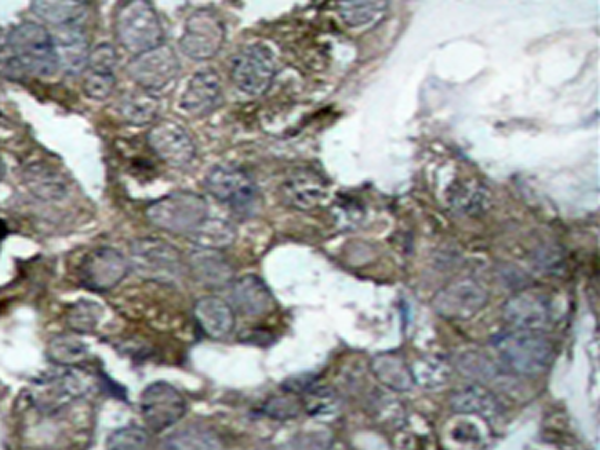

IHC positive control: |

Human breast carcinoma tissue |

IHC Recommend dilution: |

50-100 |